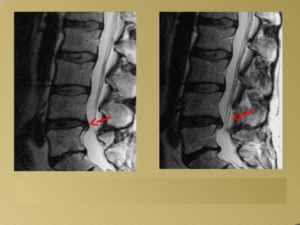

Грыжа диска наглядно

Межпозвоночная грыжа представляет собой заболевание, при котором происходит разрыв фиброзного кольца в диске позвоночника. Следует упомянуть, что такая патология не возникает в один миг, ей предшествует протрузия. В результате такого процесса пульпозное ядро, находящееся в диске, выпячивается наружу и возникает секвестрированная межпозвоночная грыжа.

Дорсальная грыжа представляет собой выпячивание пульпозного ядра без разрыва фиброзного кольца. В этом случае также существует вероятность сдавливания нервных корешков и спинного мозга, поэтому в зависимости от ситуации врачи могут использовать как консервативное, так и оперативное лечение.

Развитие грыжи от дорсальной к секвестрированной